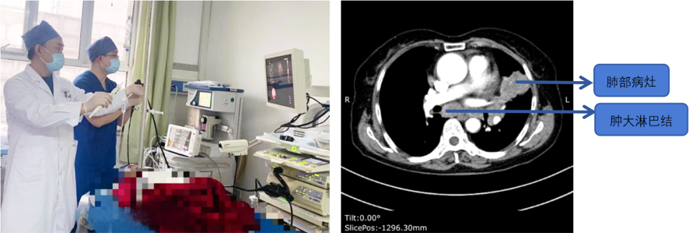

患者,女,72歲,2月來“反復(fù)咳嗽、咳痰,偶咳白痰中帶血絲”,胸部CT提示“肺占位、肺炎”,收住院。完善胸部強化CT提示“左肺占位、肺炎、縱膈多發(fā)淋巴結(jié)腫大”,電子支氣管鏡檢查見左肺上葉支氣管血塊及壞死物阻塞,清除后見管腔通暢,刷檢DNA細胞學(xué)示“細胞退變明顯,建議進一步檢查”。10月27日行CT引導(dǎo)下肺穿刺活檢,病理示“機化性肺炎”,給予抗感染及激素治療,患者癥狀好轉(zhuǎn)出院。半月前,患者復(fù)查肺CT發(fā)現(xiàn)病灶較前稍有增大,張強主任考慮患者癥狀雖有好轉(zhuǎn),但仍存在腫瘤性病變可能性。經(jīng)過討論及與患者家屬充分溝通后,決定實施支氣管內(nèi)超聲引導(dǎo)下針吸活檢術(shù)(EBUS-TBNA)+電子支氣管鏡檢查+現(xiàn)場快速評價(ROSE)技術(shù),以提高診斷陽性率。術(shù)中ROSE提示查找到可疑癌細胞,取材量較足分。最后病理檢查明確診斷為低分化肺腺癌,隨后進行基因檢測,明確了治療方向。